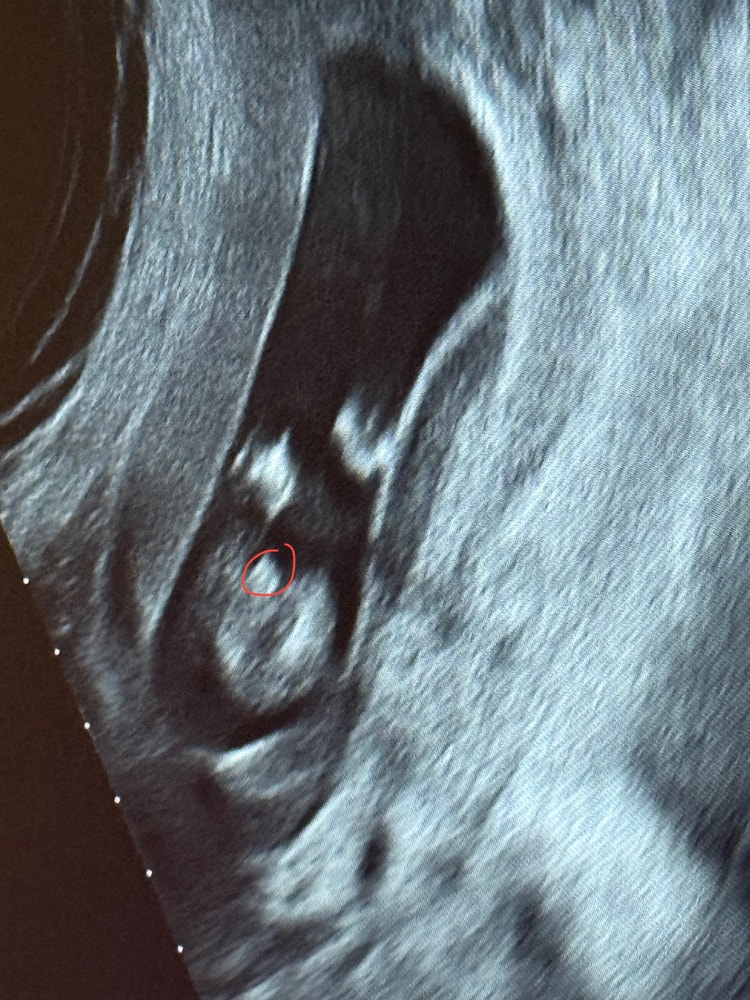

Эльза, короче я тут уже чуть ли не под лупой рассматриваю это фото😂 и вот к чему я пришла. Зеленое это всё же писюха, а красным обвела пуповину которую врач приняла за потенциальный писюн ибо мне ж сказали, что пуповина между ног Изображение Изображение